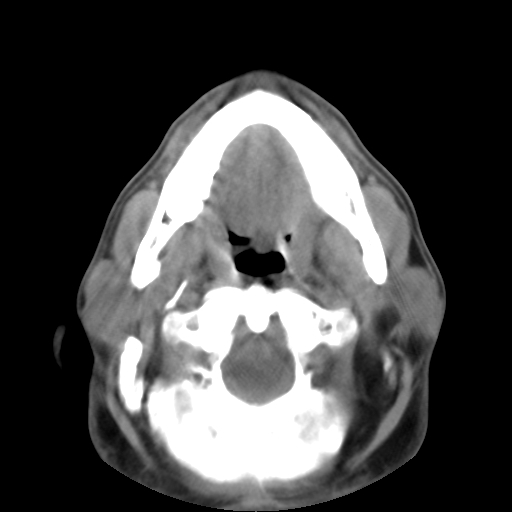

标题: CT24019:男,45岁,发现颈部肿物5个月。 [打印本页]

男,45岁,发现颈部肿物5个月,彩超示:双侧颈部及下颌部软组织增厚。

考虑双侧颈项部良性对称性脂肪增多症。